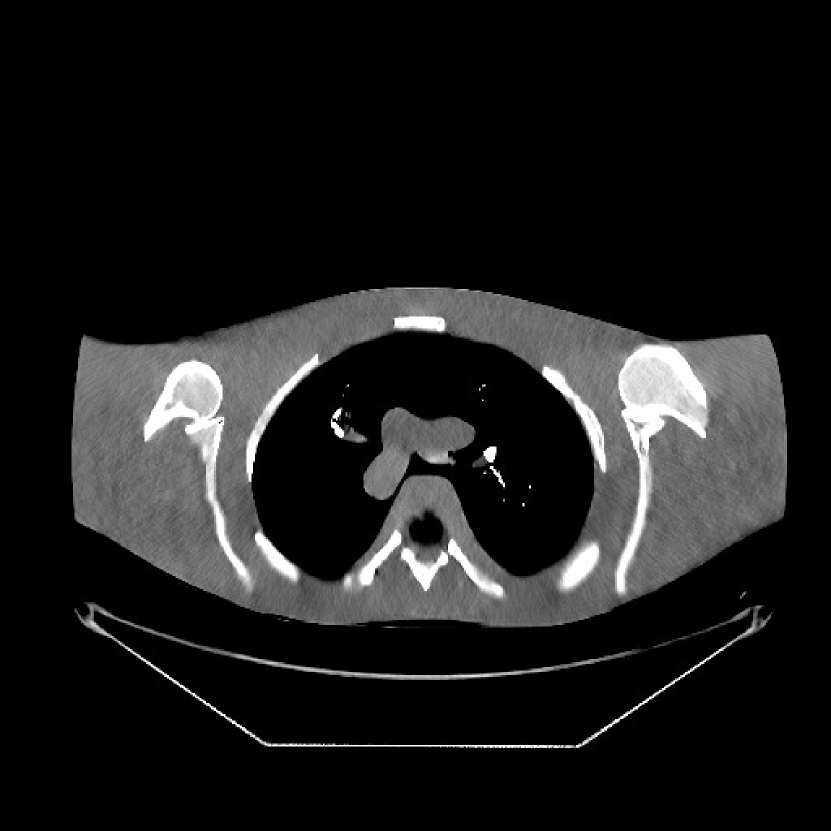

V-C1 Framework

We obtained from GE a 2D fan-beam raw (pre-log) scan of a shoulder phantom, which included the beam-hardening effect. The provided 200mA200mA200~{}\text{mA} with 1 second scan can be viewed as a standard-dose scan and all the raw measurements are positive. Based on this standard-dose scan, we simulated an ultra low-dose scan as shown in (15) with α=200𝛼200\alpha=200, and added Poisson and Gaussian noise (σ=5𝜎5\sigma=5) to the measurements. The simulated measurements have about 0.4%percent0.40.4\% non-positive values. The sinograms were of size 888×984888984{888\times 984}, and reconstructed images were of size 512×512512512{512\times 512} with Δx=Δy=0.9766subscriptΔ𝑥subscriptΔ𝑦0.9766{\Delta_{x}=\Delta_{y}=0.9766} mm.

For PWLS-ULTRA and SPULTRA, we pre-learned a union of five square transforms using 8×888{8\times 8} overlapping image patches with stride 1×111{1\times 1} from five 512×512512512512\times 512 XCAT phantom slices [38]. Here, we also compared SPULTRA with a recent deep-learning based low-dose CT denoising framework “WavResNet” combined with an RNN architecture[46]. The iterative RNN version of WavResNet was pre-trained based on the 2016 Low-Dose CT Grand Challenge data set [46]. During reconstruction, WavResNet, PWLS-ULTRA, and SPULTRA were initialized with the image reconstructed by PWLS-EP with βep=0.1subscript𝛽𝑒𝑝0.1\beta_{ep}=0.1. The parameters (β,γc)𝛽subscript𝛾𝑐{(\beta,\gamma_{c})} for both PWLS-ULTRA and SPULTRA were set as (0.05,80)0.0580(0.05,80). These values worked well in our experiment. In the supplement, we discuss in detail the parameter selection procedure of (β,γc)𝛽subscript𝛾𝑐(\beta,\ \gamma_{c}) for both PWLS-ULTRA and SPULTRA. Parameters for testing WavResNet were set according to [46], and the pixel values of the input to WavResNet were converted to match the network required scalings. Since the WavResNet was trained with images reconstructed with the filtered backprojection (FBP) method [46], we also tested on this shoulder phantom that initialized WavResNet with an FBP reconstructed image. Although initializing WavResNet with an FBP reconstructed image better matches the trained model than the PWLS-EP reconstructed image does, the latter still provided better results. We included in the supplement the denoised image initialized with the FBP reconstruction.

Fig. 10 shows the reconstructions for the 200 mA200 mA200\text{ mA} scan (reference image) along with the reconstructions for the simulated ultra low-dose scan obtained with PWLS-EP, WavResNet, PWLS-ULTRA, and SPULTRA. Visually, WavResNet fails to reconstruct the image but improves over the initial PWLS-EP reconstruction, while PWLS-ULTRA and SPULTRA provide better image quality. This indicates that the ULTRA-based methods may have a better generalization property than WavResNet, since they learn more fundamental features of CT images (also see [38]). We selected three smooth ROIs, where the pixel values are approximately constant. Tab. V(b) shows the mean and the standard deviation of pixel values for these ROIs for various methods and the standard-dose reference. Since the iterative RNN version of WavResNet only has small improvements over PWLS-EP, the pixel values do not change much compared with PWLS-EP. PWLS-ULTRA however reduces the bias in the central region of the image (ROI 2), but fails to correct the bias in the regions near the bones (ROI 1 and ROI 3). SPULTRA reduces the bias in the central region of the image, and also significantly corrects the bias near the bone regions. The standard deviations of the ROIs reconstructed by SPULTRA are comparable to those reconstructed by PWLS-ULTRA, and are close to those of the reference ROIs. Additionally, SPULTRA reconstructs the bone (indicated by the magenta arrow in the last two subfigures of Fig. 10) better than PWLS-ULTRA.